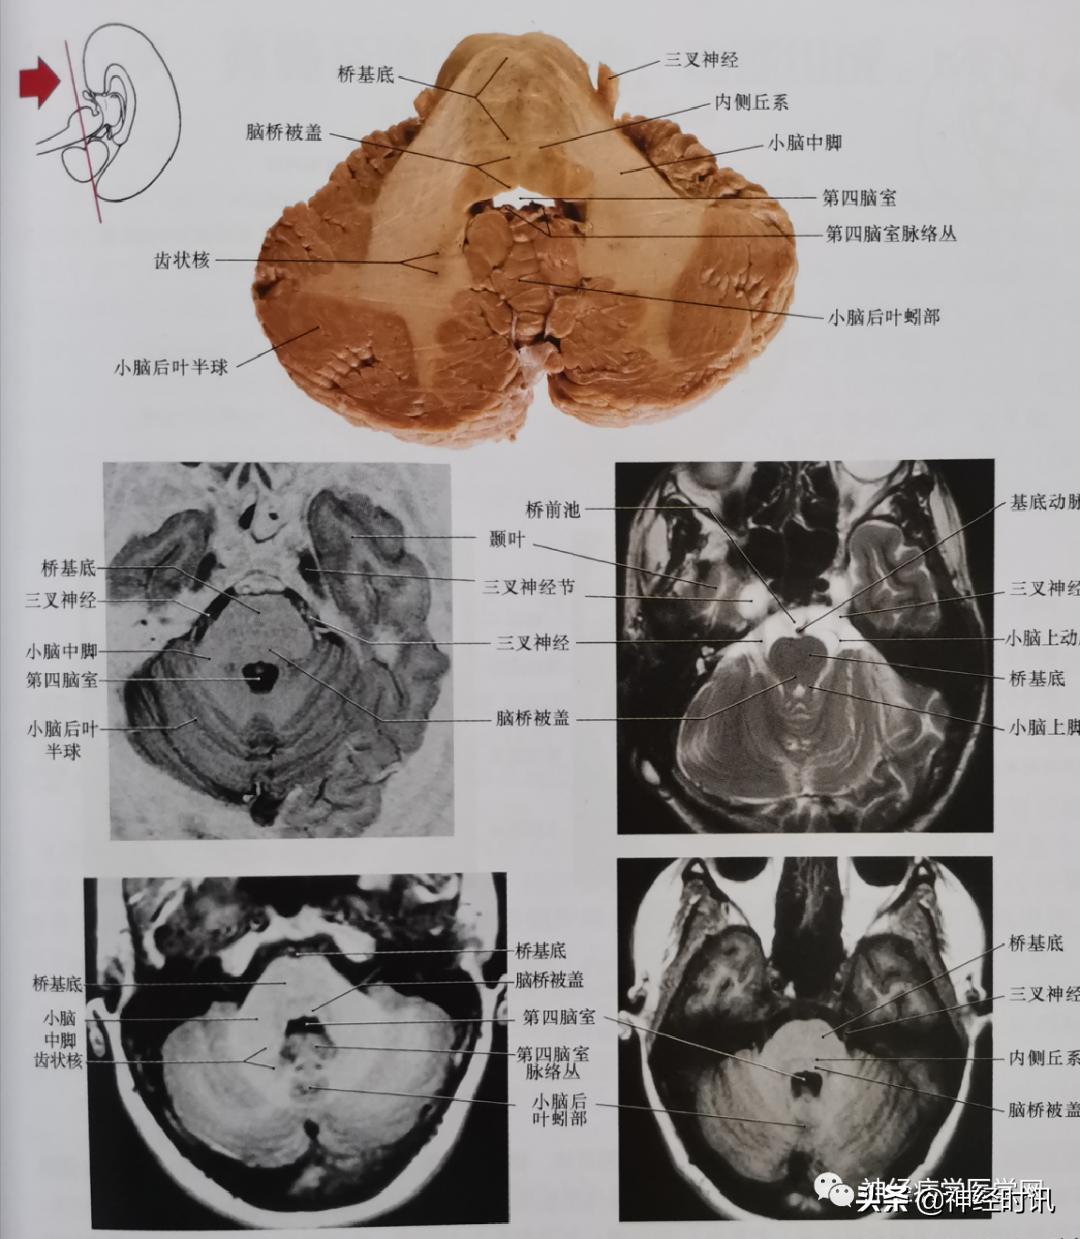

图15 通过三叉神经脑桥基部及大部分小脑中脚平面的轴位影像。此平面与脑桥基部最宽大部分及脑桥被盖相关。这4张为相同平面磁共振影像(左上方是反转技术,右上方T2,下方是T1)